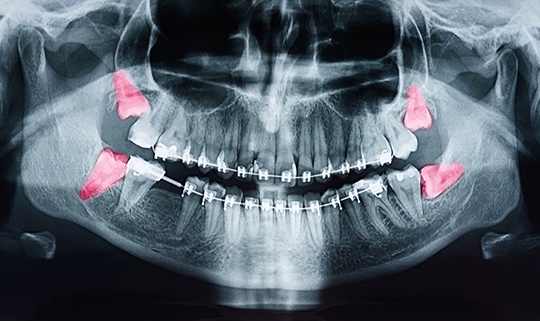

Wisdom teeth are the third set of molars that usually erupt sometime in your late teens or early twenties. Because your jaw is often too small to fit them comfortably, these teeth may come in at an angle, get stuck under your gums, or cause inconvenient crowding. And even if they don’t hurt yet, our team may monitor them and suggest removing them as a preventive measure.

Not everyone needs their wisdom teeth removed, but many people do. When these molars are impacted or poorly positioned, they can trap food and bacteria, leading to cavities, gum disease, and infection.

They may also push against other teeth, potentially undoing years of orthodontic work or damaging underlying structures. For example, in some cases, cysts can form around impacted teeth and damage your jawbone.

Before your treatment, our team will take detailed X-rays and review your medical history so we can plan a safe, efficient procedure. On extraction day, your dentist will numb the area completely to ensure you don’t feel any pain.